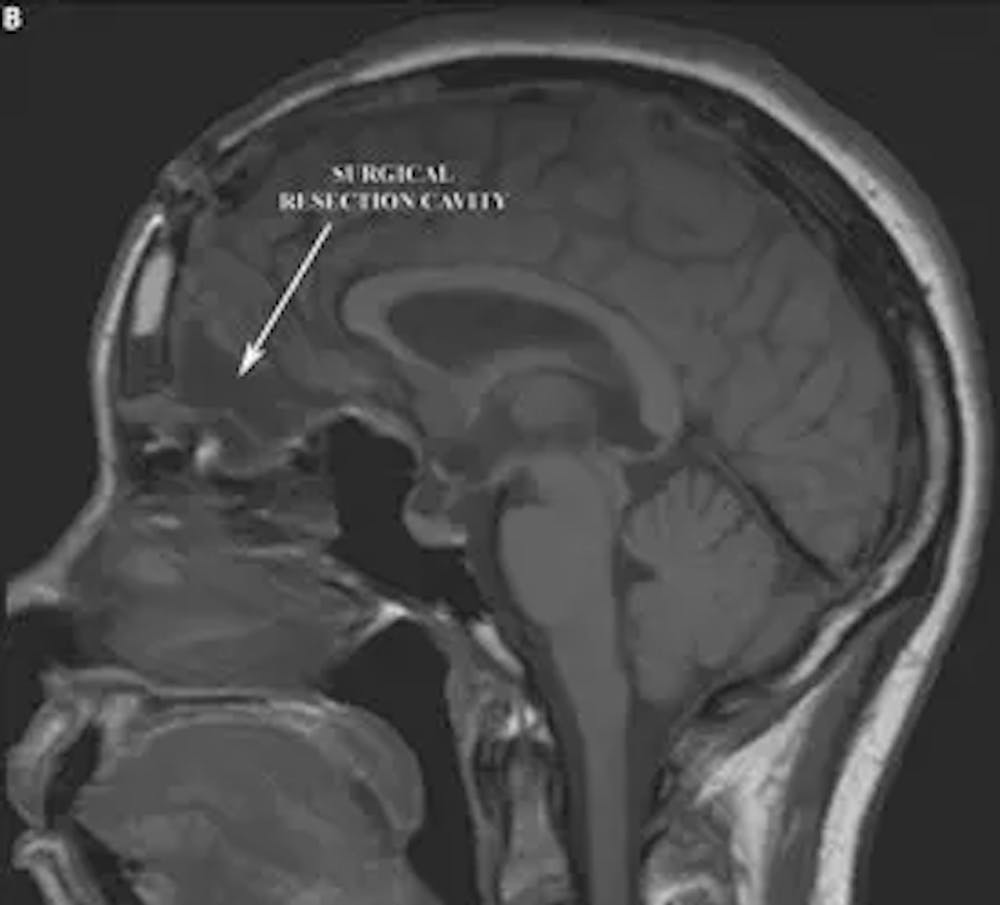

એ) પ્રિ-ઓપરેટિવ સગિટલ T1 એમઆરઆઈ કોન્ટ્રાસ્ટ સાથે આગળના લોબને સંકુચિત કરતા મોટા મેનિન્જિયોમા દર્શાવે છે

બી) પોસ્ટ-ઓપરેટિવ સગિટલ T1 એમઆરઆઈ રિસેક્શન કેવિટી અને આગળના લોબ્સ પર સામૂહિક અસરનું રિઝોલ્યુશન દર્શાવે છે